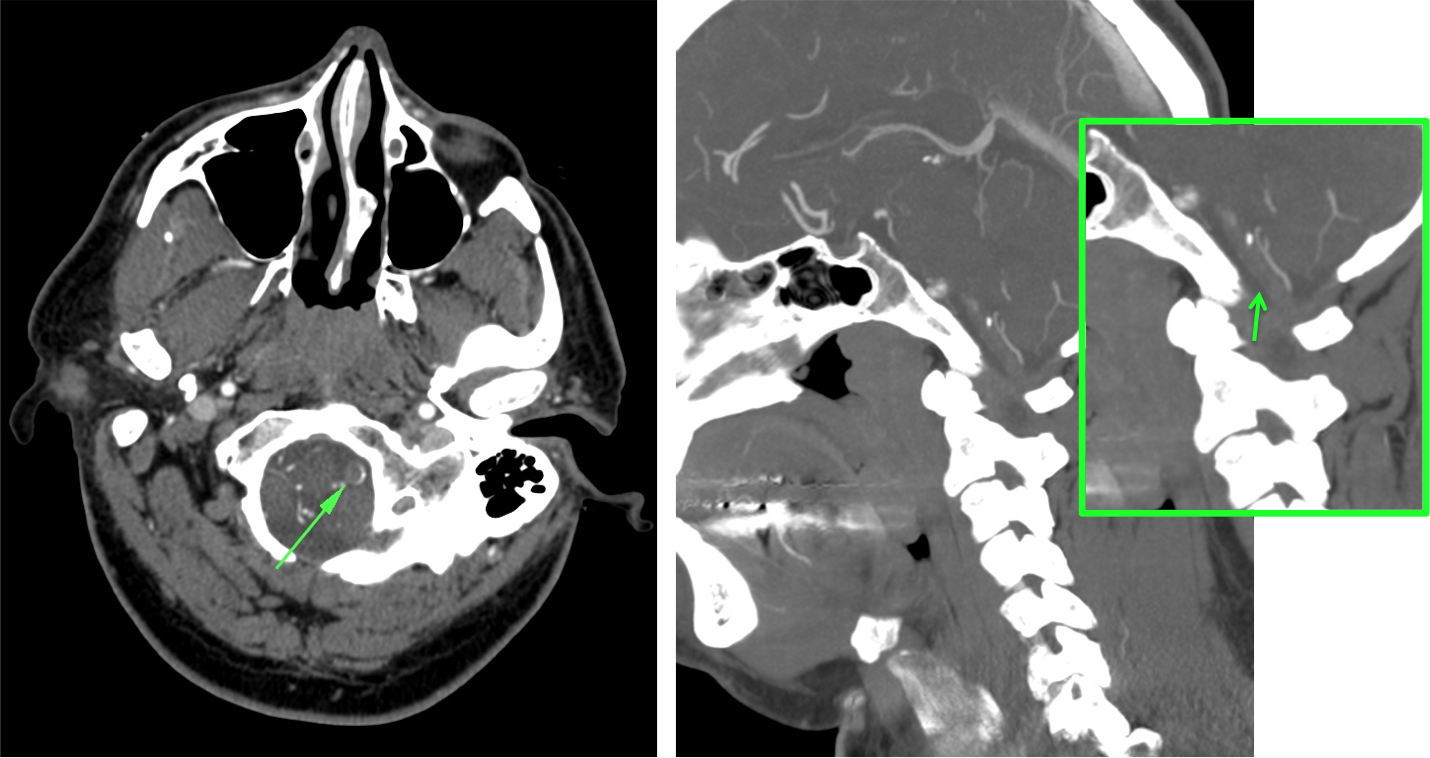

ANGIOGRAFÍA TC.

Sirve para:

- Definir el lugar de oclusión.

- Descartar disección arterial.

- Grado de colateralidad.

- Grado de arterioesclerosis.

Con la información aportada podremos pronosticar mejor la localización y extensión del infarto. Además, proporciona un mapa vascular para el tratamiento endovascular.

La angioTC nos sirve para:

- Detectar trombosis: informar acerca de la apariencia, localización, dimensiones. Localizaciones frecuentes:

- Tándem ACI-ACMedia

- Tronco Basilar

- Región carotídea.

- Segmento M1 de ACM

- Segmento M2 de ACM

- Detectar disección arterial (produce ictus por suelta de embolos o por oculisón hemodinámica)